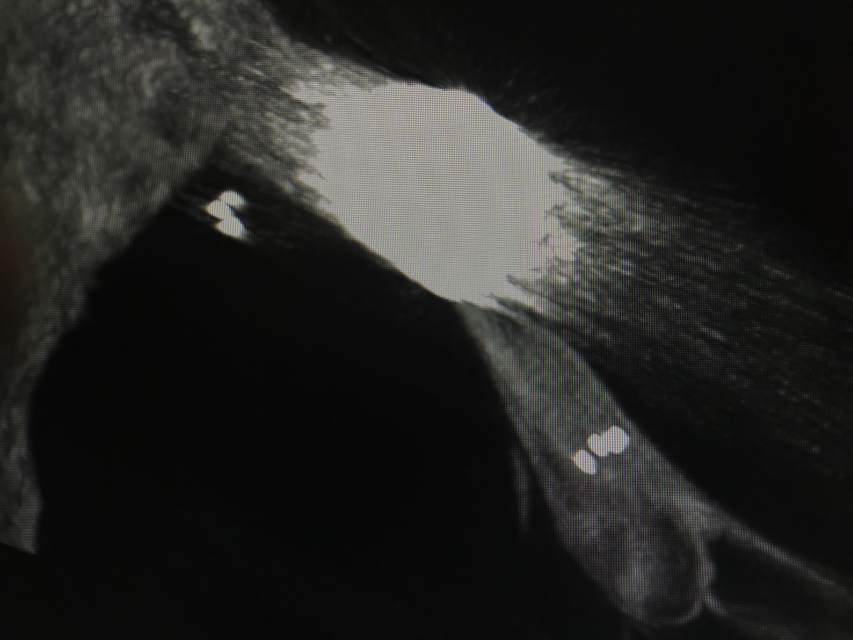

福建中年女性,近期在外查出“颅内动脉瘤”,经推荐转来我院诊治。患者的颈内动脉通路迂曲,动脉瘤也位置奇特,解剖复杂,动脉瘤远近段的血管弯弯绕绕,重重叠叠,眼花缭乱,难以兼顾找到最佳位置。最终克服困难,将“基底型”动脉瘤改变为“侧壁型”动脉瘤,顺利给予治疗……